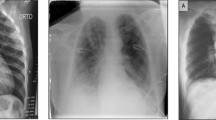

The host medical image is taken from the dataset13,14,15,16,17. These are medical images that shows a covid-infected lung images, pneumonia images, Brain tumor images, Breast ultrasound images, lung CT scan images. This image is preprocessed for the experiment, converted to a grayscale picture of size 512*512, and shown in Fig. 2. The Watermark taken is self-generated. It is black and white, with the size of 64*64 and shown in Fig. 4.

The propounded algorithm is experimented with using HMI as 2 randomly selected brain tumours15, 2 chest Xray16, 2 Breast Ultrasound14, 2 COVID-19 CT-Scan13, and 2 COVID-19 Xray17. They are shown in Fig. 2. All the HMIs were pre-processed to size 512*512 and grayscale. The W considered for the propounded algorithm is shown in Fig. 4 and is in size 64*64 and in black and white nature. The attacks are listed in Table 2. The propounded method shows promising results against the no-attacks and attacks and adequately balances the robustness and imperceptibility. Addition to it, security and effectiveness is also ensured by getting satisfactory results of NPCR and UACI. The primary motivation of the propounded algorithm is to provide an extra dimension of security to the watermark by scrambling it before watermarking it to the HMI. The results of the propounded watermarking techniques are also compared with those of competent methods. Simulation parameters specifications are tabulated below in Table 2.